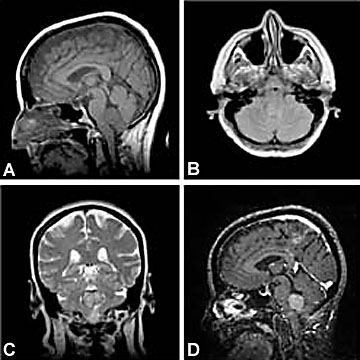

A) Sagittal T1; lesion slightly hypointense to adjacent brain

(B) Axial Proton Density; slightly hyperintense to adjacent brain

(C) Coronal T2; minimal more hyperintensity than on PD with rim of hypointensity

(D) Sagittal Gradient T1; lesion enhances moderately with Gado.